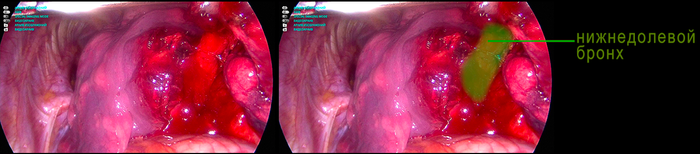

Следующий этап – бронх нижней доли. Вот он

Разделение легкого и прошивание бронха у меня на видео не попало. Короче, доля удалена, теперь ее нужно извлечь. Для этого в полость погружается контейнер, а в него погружается доля, затем извлекается (само извлечение на видео не попало).